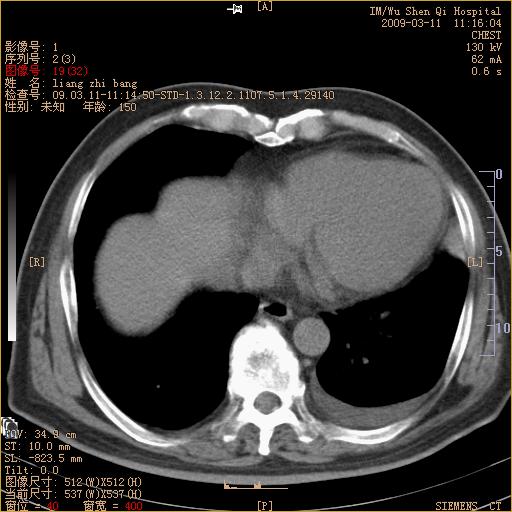

标题: CT18604:男,60岁,咳嗽一月余 [打印本页]

标题: CT18604:男,60岁,咳嗽一月余

1)考虑左肺上叶中央型肺癌并左肺上叶肺不张;建议必要时行纤支镜检查进一步明确诊断。2)左侧胸腔积液。

肺门肿块、支气管开口闭塞伴肺不张及胸水!典型的中心型肺癌变现!

1、左肺上叶中央型肺癌并上叶阻塞性肺不张。

2、左侧胸腔少量积液,右侧胸膜轻度增厚。

左肺们肿块并左肺上叶不张。考虑左肺中心性肺癌并左肺上叶不张及左侧胸腔积液